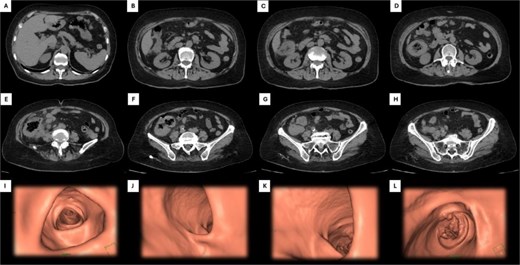

An abdominal computed tomography (CT) scan revealed concentric and diffuse thickening of the ascending colon, up to 15 mm in diameter, extending from the ileocecal valve to the hepatic flexure. Submucosal enhancement with pericolic fat stranding, mesenteric lymphadenopathy, and a right inguinal mesenteric nodule were observed, along with pulmonary nodules up to 23 mm in the left lung base (Fig. 1).

Abdominal CT and 3D colonoscopy. Images A–H depict the descending sequence of axial CT slices, with the white arrow indicating the lesion at the colonic level. Images I–L correspond to selected views from a virtual colonoscopy: Image I shows the transverse colon, J the hepatic flexure, K the ascending colon and cecum, and L highlights the lesion located in the cecum.